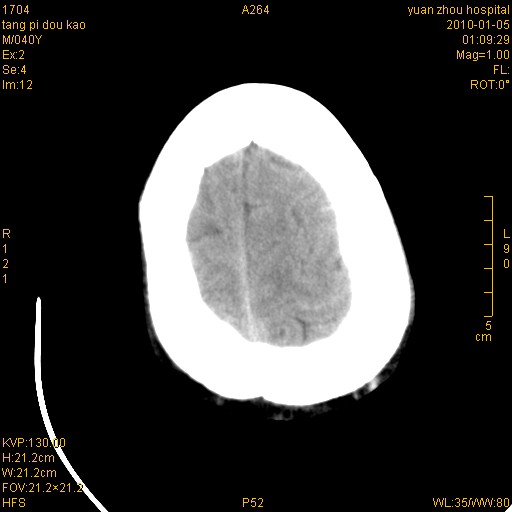

1)左侧颞枕部硬膜外血肿。2)右侧额部硬膜下血肿。3)双侧额叶及右侧基底节下部脑挫裂伤。4)蛛网膜下腔出血。5)脑水肿。6)左侧前组筛窦及左侧额窦炎症。

弥漫性脑轴索损伤

病人很清醒。